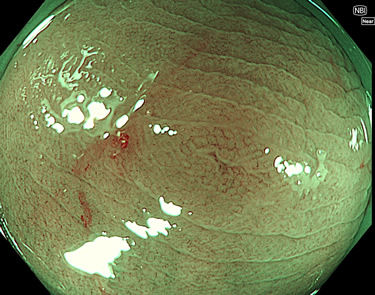

完全に平坦な物をUb、陥凹している物をUcと呼びます。Ubは認識が困難で、Ucはびらん(炎症)と紛らわしいために見落とされやすく、「内視鏡後・大腸癌」の原因になります。

専門的)Uc=De Novo癌? 内視鏡の解像度が低かった時代、このような説もありました。しかし今日の高精度内視鏡では良性の微小なUc型腺腫(APC遺伝子異常の腺腫)が日常的に見つかります。Ucこそが多段階発癌(Adenoma-Carcinoma Sequence)のMain Routeです。

毎週の検査(木・金・土・日)に発見されたUbとUc型・腺腫を、その週の日曜の夜にUPし1週間、提示します。

2025年10月16日〜10月19日の4日間(40件)2個 (Uc_ADR=2個/40人=5%)